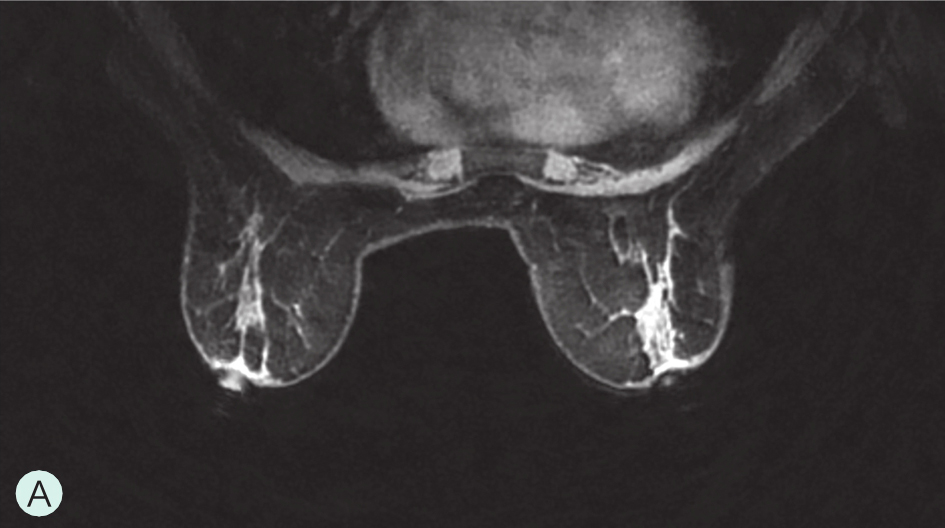

图1-3-3 乳腺MRI不同乳腺密度

A.脂肪型;B.散在致密型;C.不均匀致密型;D.极度致密型